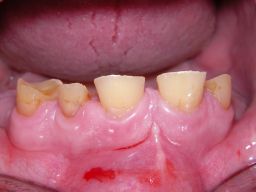

Hier ein einfacher Fall, bei dem keine besondere Vorbehandlung notwendig war. Der Patient, 58jährig, suchte die Praxis erstmals im September 2005 auf. Es erfolgten mehrere prothetische Planungen, der Gutachter des "Medizinischen Dienstes der Krankenkassen" (MDK) wurde noch von der Krankenkasse in Anspruch genommen, was heute bei größeren Planungen der Regelfall geworden ist. Umgesetzt wurde dann eine für einen solch großen Fall preisgünstige Lösung von 6434 Euro Gesamtkosten (4264 Laborkosten, 2170 Honorar). Die Krankenkasse übernahm als Festzuschuß 3843 , für den Patienten verblieben 2591. Im Januar 2006 ging es dann endlich los - zunächst allerdings beim Kieferchirurgen, weil wegen einer erhöhten, medikamentös bedingten Blutungsneigung es sicherer erschien, einige Zahnentfernungen von diesem durchführen zu lassen. Ausgangsbilder: |

Die Bilder können alle angeklickt werden! Das Hauptproblem dieses Falles lag im Oberkiefer - die über die Jahrzehnte abgeknirschten, kurzen Zähne erschweren Kronen, die durch eine Prothese belastet werden können. Die gewählte Lösung besteht darin, die Zähne nur rundherum zu beschleifen, aber nicht mehr zu kürzen und die Prothese mit einem Druckknopfsystem an die Zähne anzukoppeln, das ein "Spiel" aufweist, so daß die Prothese nicht als Hebelarm auf die schwachen Restzähne wirken kann. Rechts die beschliffenen Zähne kurz vorm Zementieren der Kronen. |